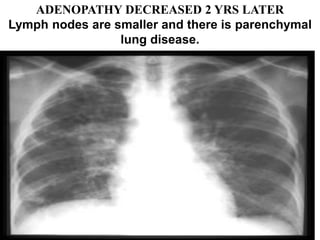

ADENOPATHY DECREASED 2 YRS LATER

Lymph nodes are smaller and there is parenchymal

lung disease.